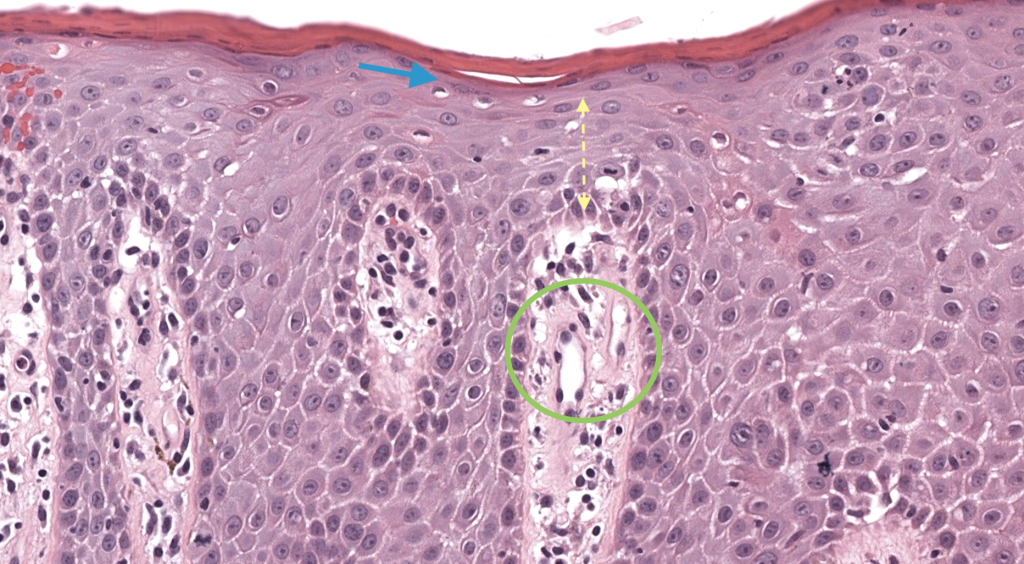

Biopsia punch solo si atípico/duda. Balan 2021